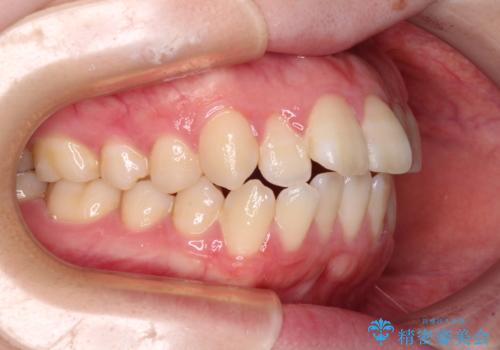

強い舌の突出癖により、上下前歯が前方に飛び出しており、特に上顎前歯は下顎よりも更に前方に位置している状態でした。

上顎前歯をしっかりと後方に移動させるため、口蓋側にアンカースクリューと補助装置を併用し、上下左右の第一小臼歯4本を抜歯し、ワイヤー装置にて矯正治療を行うこととしました。